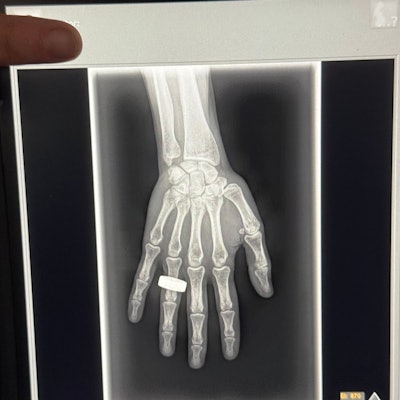

The commander of the Fen2 space mission has posted on social media what may be the first x-ray image taken in space.

In an April 1 post on the social media platform X, Chun Wu wrote that on the second morning of the flight, the crew woke up, had breakfast, and “took a few x-ray images.”

The post has received over 14.9 million views at the time of writing. The image appears to be a nod to the first x-ray ever taken by Wilhelm Roentgen of his wife Anna Bertha Ludwig's hand on December 22, 1895.

The Fen2 mission launched on March 31 and is expected to be in orbit for at least another day. The crew is conducting more than 20 science experiments, including taking images of each other with an ultraportable x-ray machine.